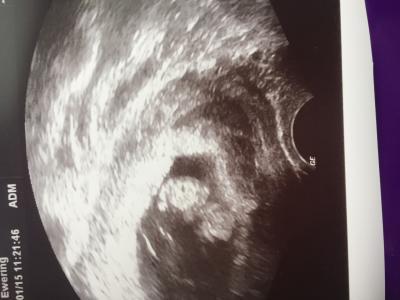

Also gestern gings wieder zum FA! Ich war schwer nervös... Irgendwie war da die Angst in mir dass es sich nicht weiter entwickelt hat. ABER falsch. Knubbel ist 7cm groß und hat ganz wild gezappelt beim Schall. Erst hat es uns den Rücken zu gedreht, aber dann hats sich riiiichtig schön gedreht und gestreckt! Verrückt,... Es fühlt sich immernoch an, als wäre das ein Film und nicht in mir. Geht's euch auch so? Alles sehr surreal. :D Ach noch was; meine FÄ hat ein kleineres Hämatom (?) in der Nähe der fruchtblase gefunden. Das geht vielleicht irgendwann ab, blutet dann, aber macht nix. Vielleicht habt ihr ja was ähnliches. Nicht jede Blutung ist also gleich eine totale Katastrophe. Trotzdem; alles abklären lassen. Das Hämatom kommt durch die Dehnung der Gebärmutter;-) Und nu das Bild :)

Bild zu Sooo dann kann ich unser knubbelchen auch zeigen :) - Forum für August - Mamis

Wie süß. Sieht aus, als hätte es ein Zipfelmützchen auf

Das sieht aus wie ein Schlumpf :) Finde auch immer wieder beeindruckend, dass da jmd in meinem Bauch wohnt

Edina; meine FÄ sagte dass es daher kommt, also alles gut ;-) Ja 7cm laut dem ultraschallbild- die Messen ja immer Scheitel bis "sohle" also die ganze Länge - ich bin auch erschrocken als ich eure 4 cm gelesen hab :D aber das reguliert sich alles, denk ich! Ärztin meinte es wäre ganz zeitgemäß :)

Das ist dann wohl die Erklärung. Normal ist Scheitel-Steiss-Länge. Klar,dass Scheitel-Sohle dann riesig wirkt. SSL ist normal Scheitel-Steiss. Also keinen Schrecken bekommen, wenn du mal an einen anderen Arzt gerätst. Glückwunsch zur tollen Untersuchung und dem Bildchen!